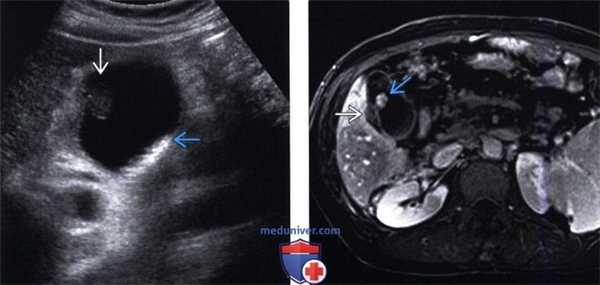

(Левый) У пациента с циррозом на поперечном УЗ срезе визуализируется крупный, несколько менее эхогенный полип на тонкой ножке и смещающиеся книзу под действием гравитации конкременты желчного пузыря.

(Правый) У этого же пациента при Т1-взвешенной с контрастным усилением МРТ в отсроченную фазу на аксиальной томограмме визуализируется гладкий контрастный полип желчного пузыря. Также отмечается отек прилегающей стенки желчного пузыря.